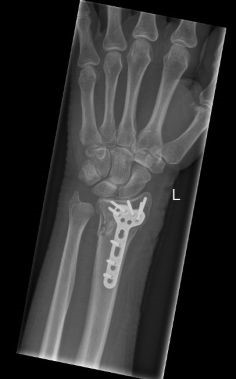

Operatie bij volwassenen

Indien er sprake is van een ernstige breuk met een slechte stand (ondanks zetten) of wanneer wordt ingeschat dat de stand van de breuk nog verder zal verslechteren, dan kan de traumachirurg samen met u bepalen dat er een indicatie is voor een operatie. Hiervoor zijn er meerdere opties. Het meest wordt er gebruik gemaakt van een plaatje en schroeven voor het vastzetten van de breuk. Soms wordt er ook gebruik gemaakt van stevige staaldraden of van een fixatie aan de buitenkant (zogenaamde ‘externe fixateur’).

Zoals elke operatie, heeft ook een operatie voor een gebroken pols kans op complicaties, zoals ontstekingen van de wond, pijnklachten, pees-, vaat- of zenuwletsel en het loslaten van het fixatie materiaal en het alsnog verplaatsen van de breuk. Welke operatie u krijgt, is afhankelijk van de eigenschappen van de breuk en de toestand van de huid en de spieren. Uw traumachirurg bepaalt of het nog nodig is om na de operatie nog tijdelijk gips te krijgen.